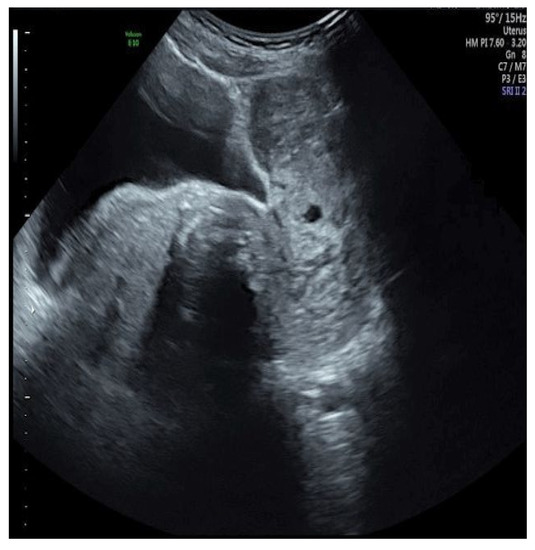

| Case Described by This Article | 50 | Yes | LPT Pfannenstiel | US + CT | 10 cm × 9 cm × 7 cm | Paraovarian mass | Mass only |